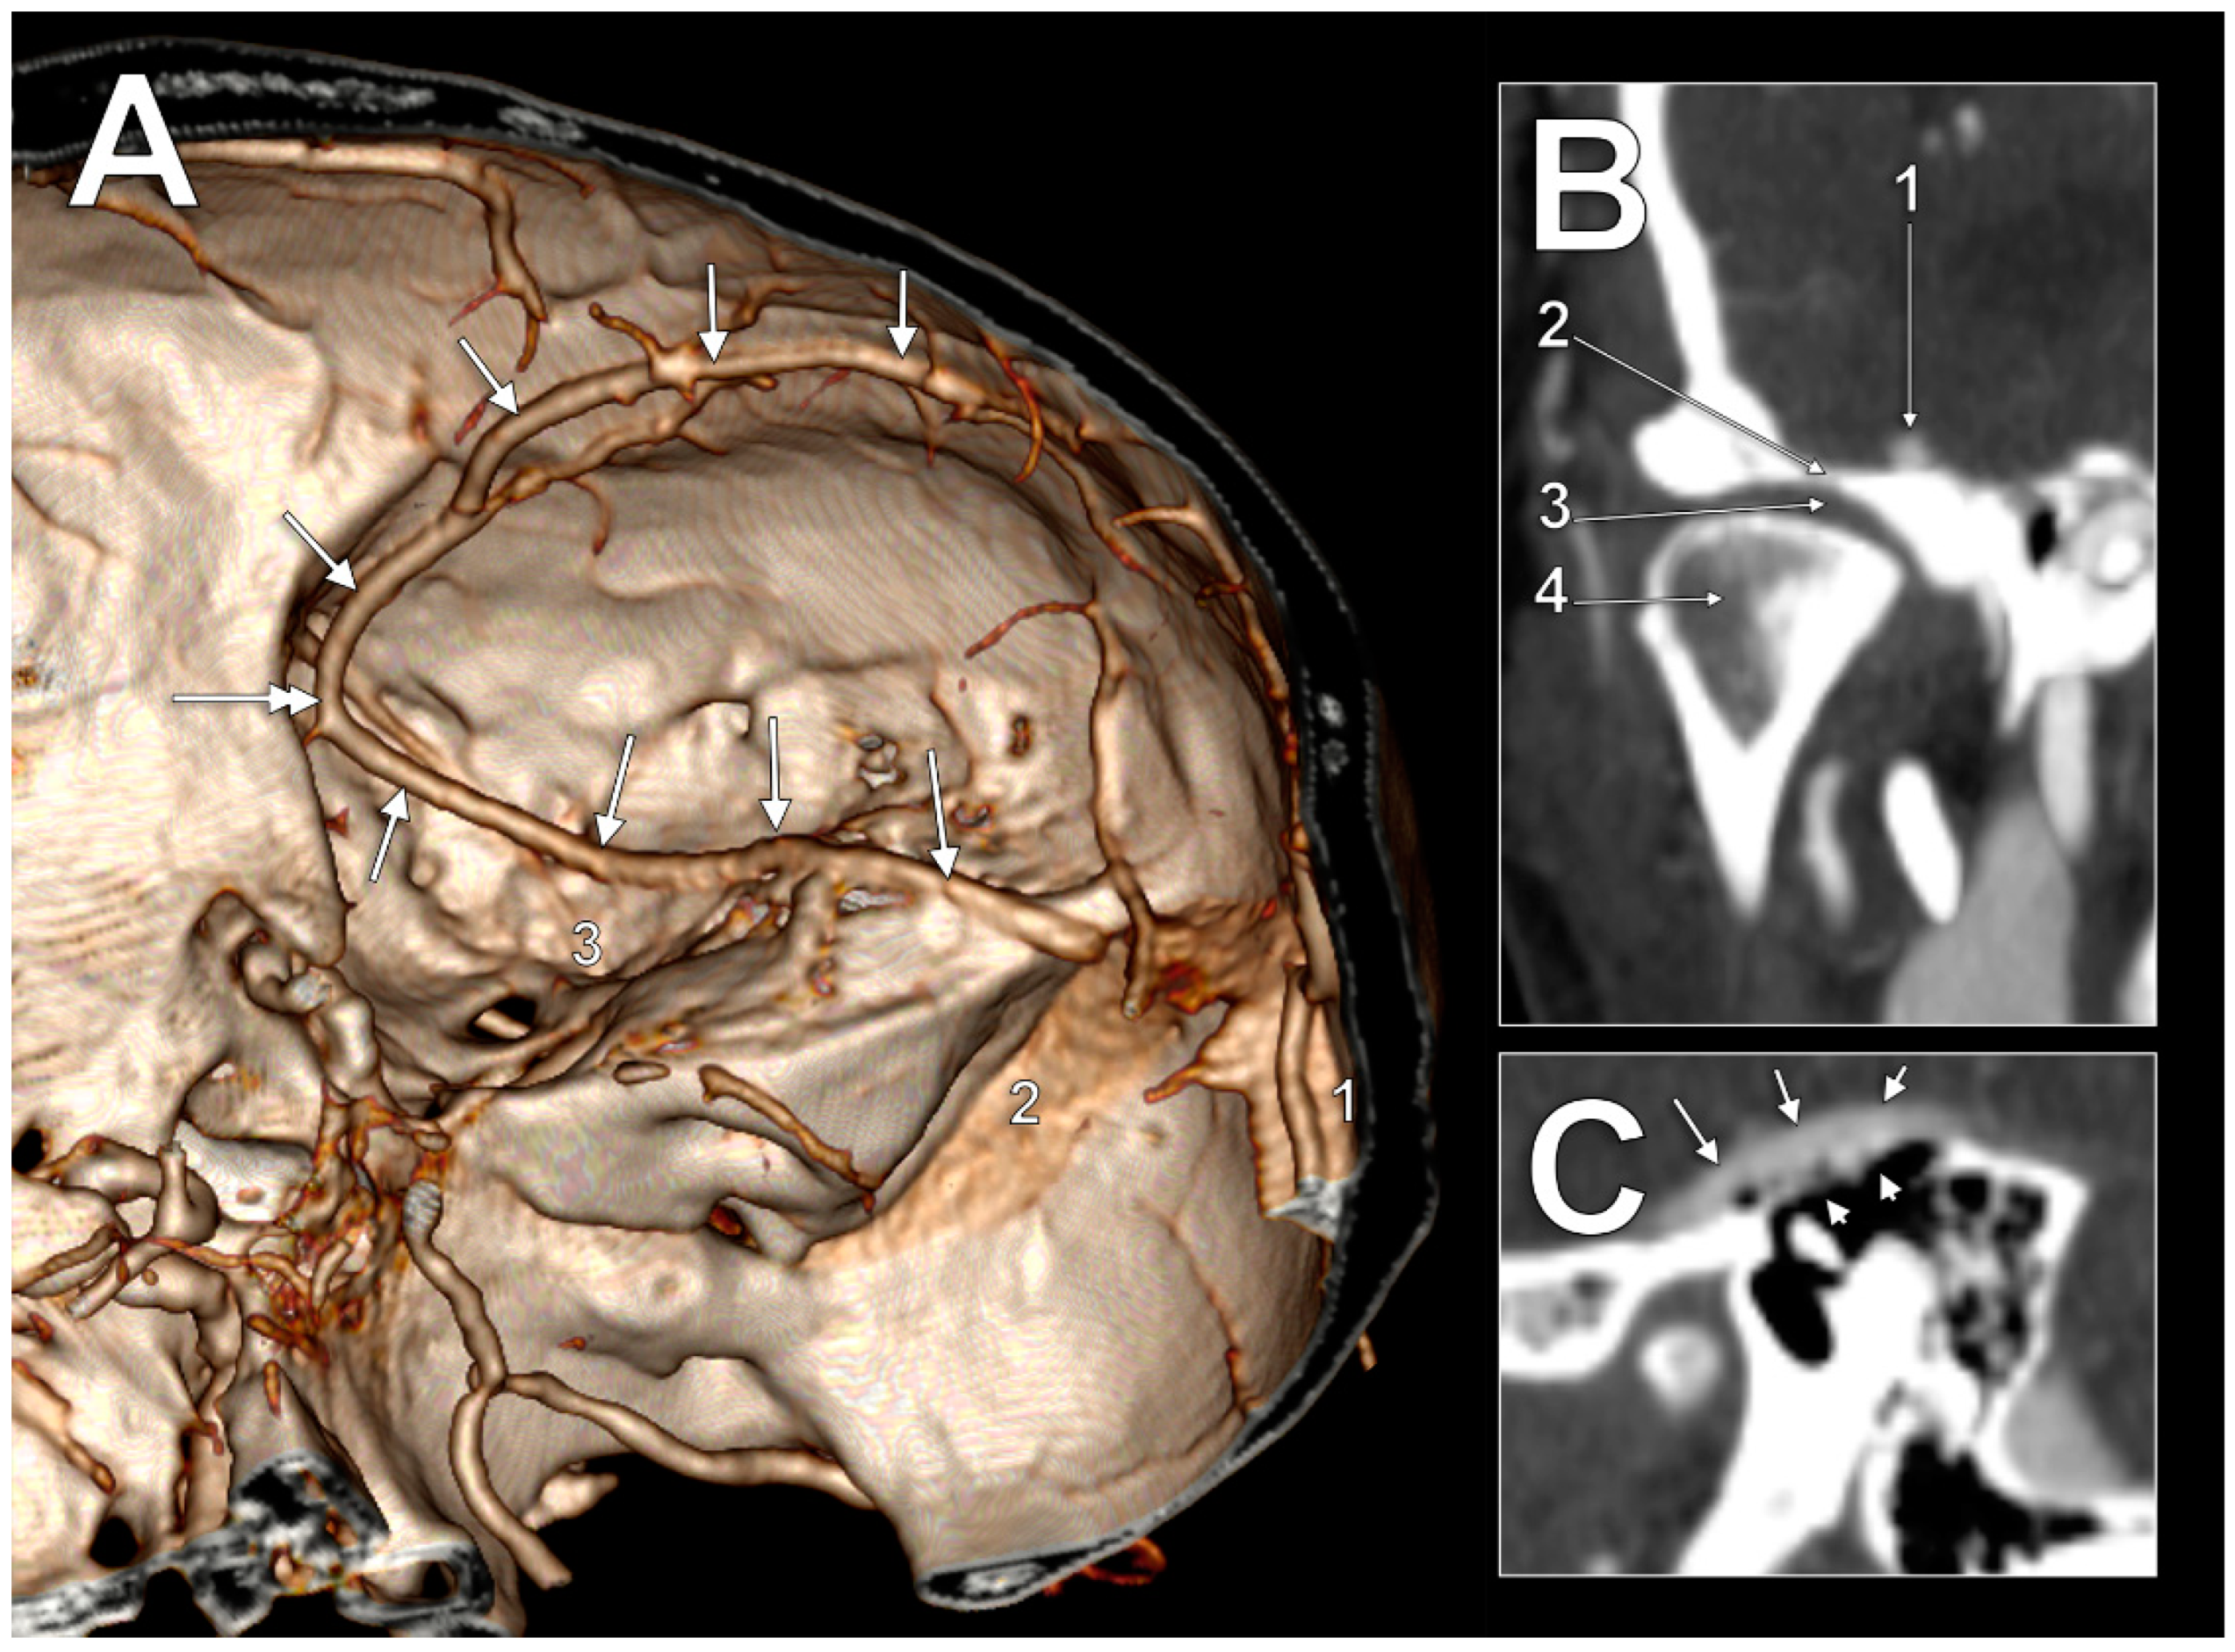

In the first case (Figure 1A), the SMCV had an initial postero–anterior course, superficially, in the Sylvian fissure. At the pterion level, it continued descending on the temporal lobe to until it was posterior to the lateral part of the superior orbital fissure, where it formed a sagittal loop on the medial side of the anterior branch of the middle meningeal artery to further continue anteroposteriorly on the middle cranial fossa floor. In the middle fossa, it had four segments: (1) an alar segment on the greater sphenoidal wing; (2) a squamosal segment on the horizontal part of the temporal squama; (3) a petrosal segment on the petrous part of the temporal bone; and (4) a mastoid segment, on the mastoid part of the temporal bone. The alar segment coursed at 1.1 cm lateral to the foramen ovale and at 5.1 mm lateral to the foramen spinosum and the entry of the middle meningeal artery. Then, it continued as the squamosal segment. The squamosal segment was first located above the articular eminence, then above the inner part of the mandibular fossa (Figure 1B) above the temporomandibular joint. The following petrosal segment coursed above the tympanic cavity at 3.4 mm from the head of the malleus. The tympanic roof (tegmen tympani) was thinned/dehiscent (Figure 1C). The last mastoid segment coursed obliquely above the mastoid air cells to posteromedially drain into the junction of the right transverse and sigmoid sinuses.

Figure 1. (A) CT angiography, three-dimensional volume rendering of the right superficial middle cerebral vein (SMCV) of the basal type (arrows). Superomedial view. 1. transverse sinus; 2. sigmoid sinus; 3. foramen spinosum. The sagittal loop of the SMCV is indicated (double-headed arrow). (B) Coronal CT slice through the right temporomandibular joint. 1. superficial middle cerebral vein; 2. mandibular fossa; 3. articular disc; 4. mandibular condyle. (C) Sagittal CT slice through the right tympanic cavity. The superficial middle cerebral vein (arrows) courses on a dehiscent tympanic roof (arrowheads).